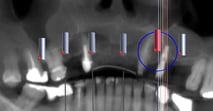

PRÓTESE SOBRE IMPLANTE PROTOCOLO

A prótese protocolo é uma solução fixa sobre implantes, utilizada para substituir todos os dentes de uma arcada dentária (superior ou inferior). Esta técnica oferece uma prótese estável, confortável e com uma aparência muito natural.

Tomogafia computadorizada, para analise ossea e escaneamento, para planejamento dos futuros dentes

Protese Protocolo finalizada, seguindo etapas de seleçao de cor de dentes e gengiva e provas estéticas, sempre com a participaçao do paciente em todo o processo.

Guia cirúrgico para posicionar os implantes, no momento da cirurgia, de acordo com o planejamento do novo sorriso.

Cirurgia com equipe especializada para instalação dos implantes